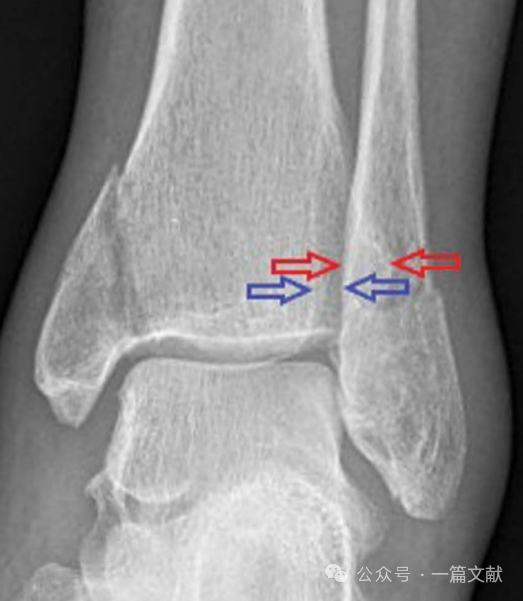

1,透视正位及踝穴位片,来观察胫腓骨重叠距离如下图红色箭头之间距,若标准正位片上此距离小于6mm,或踝穴位片小于1mm则考虑下胫腓不稳定。或者于关节面以上1cm处观察胫腓骨间隙如下图蓝色箭头之间距,与健侧相比,若增加2mm以上,则考虑下胫腓不稳定

图片